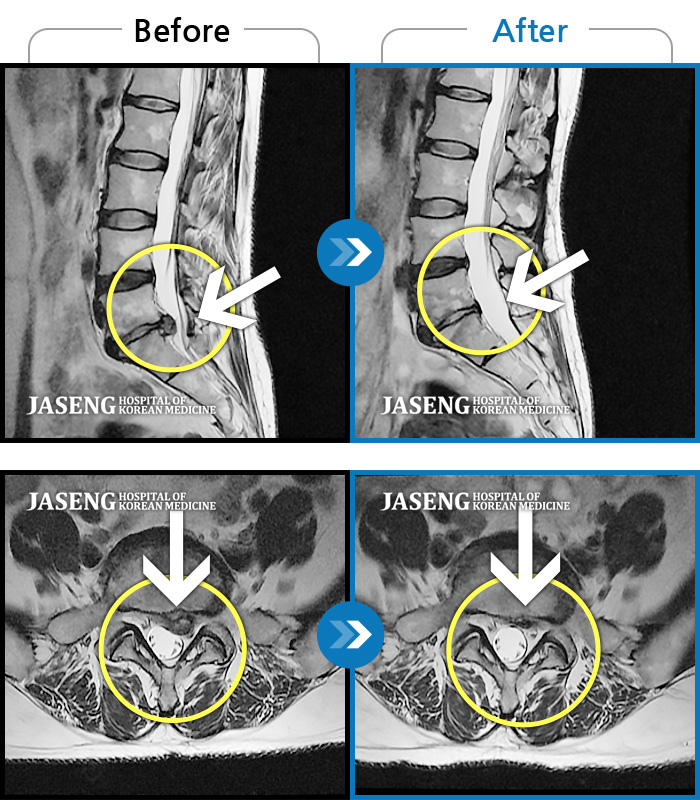

Before

After

환자에게 사전 동의를 받아 동일 조건에서 촬영되었습니다.

개인에 따라 치료 후 부작용이 발생할 수 있으니 의료진과 상담 후 치료를 진행하시기 바랍니다.

허리 디스크 수술 후 재발된 디스크 환자

허리 및 우측 하지 통증